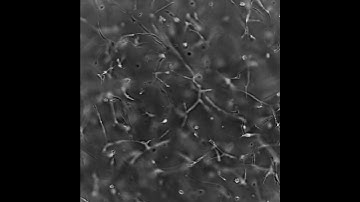

Utilization of fibrin hydrogel for the encapsulation of cardiomyocytes in cardiac tissue engineering